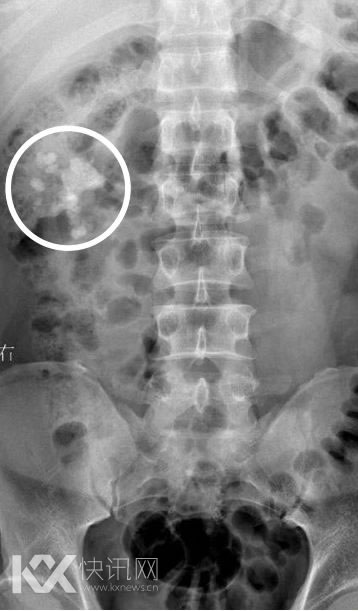

唐先生在医院拍的X光片,图圈系结石,图由医院提供。(图片来源:成都商报)

去年8月的一天,唐先生回到三台县老家,一天傍晚在二楼乘凉后,从二楼纵身一跃,跳到一楼地面。起身后,他就开始疼痛难忍,经三台县医院检查,他并未闪腰,而是双肾长满了结石,右肾有数颗结石,最大长度达到7厘米,左肾则只有几颗小结石。他从二楼的一跳,让右侧肾脏中的一颗较小结石掉入了输尿管,梗阻了尿路,引起了钻心的肾绞痛。

今年1月中旬,唐先生经朋友介绍来到成都一家结石病医院。经检查,他左肾中的确没有再发现结石,而右肾仍为“多发结石,重度积水”。